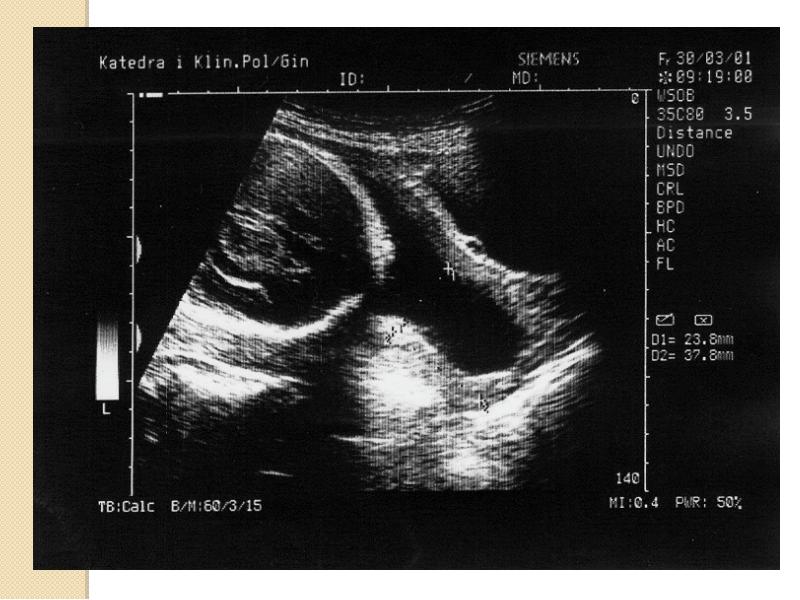

- 45. Niewydolność cieśniowo-szyjkowa Badanie USG Średnia długość szyjki macicy 38-42mm Długość

- 46. Niewydolność cieśniowo-szyjkowa Badanie USG przez powłoki brzuszne: wymaga wypełnienia pęcherza moczowego.

- 47. Niewydolność cieśniowo-szyjkowa Badanie przezpochwowe: pęcherz moczowy musi być opróżniony. należy zidentyfikować